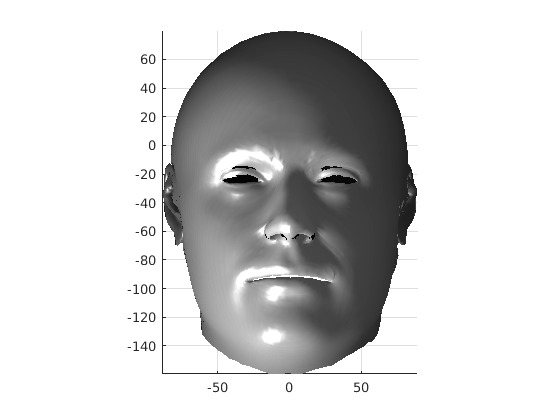

Following this, OSNR ICP iterates over a set of decreasing mesh stiffnesses (typically 10), until the registration between the template and the scan is below some error or a maximum number of iterations is reached. Figure 28 shows a selection of template warp results. The template appears to be accurately warped onto the scan, at least in the normal direction of the surfaces, it is not possible to see error tangential to the surface. Furthermore, we have noted errors on some scans on the ears. To improve these we need a method of automatically landmarking the ears, which is an area for further work.

|

|

|

|

|

|

|

|

The first two modes of head variation are shown in figures 29 and 30. These include the cranial height / facial angle mode and the (almost) pure size mode, as seen in the sagittal profile model.